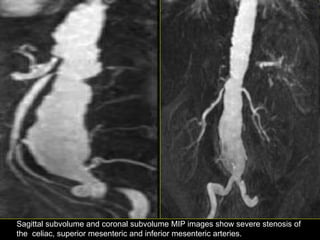

Sagittal subvolume and coronal subvolume MIP images show severe stenosis of

the celiac, superior mesenteric and inferior mesenteric arteries.

Sagittal subvolume andcoronal subvolume MIP images show severe stenosis of the celiac, superior mesenteric and inferior mesenteric arteries.